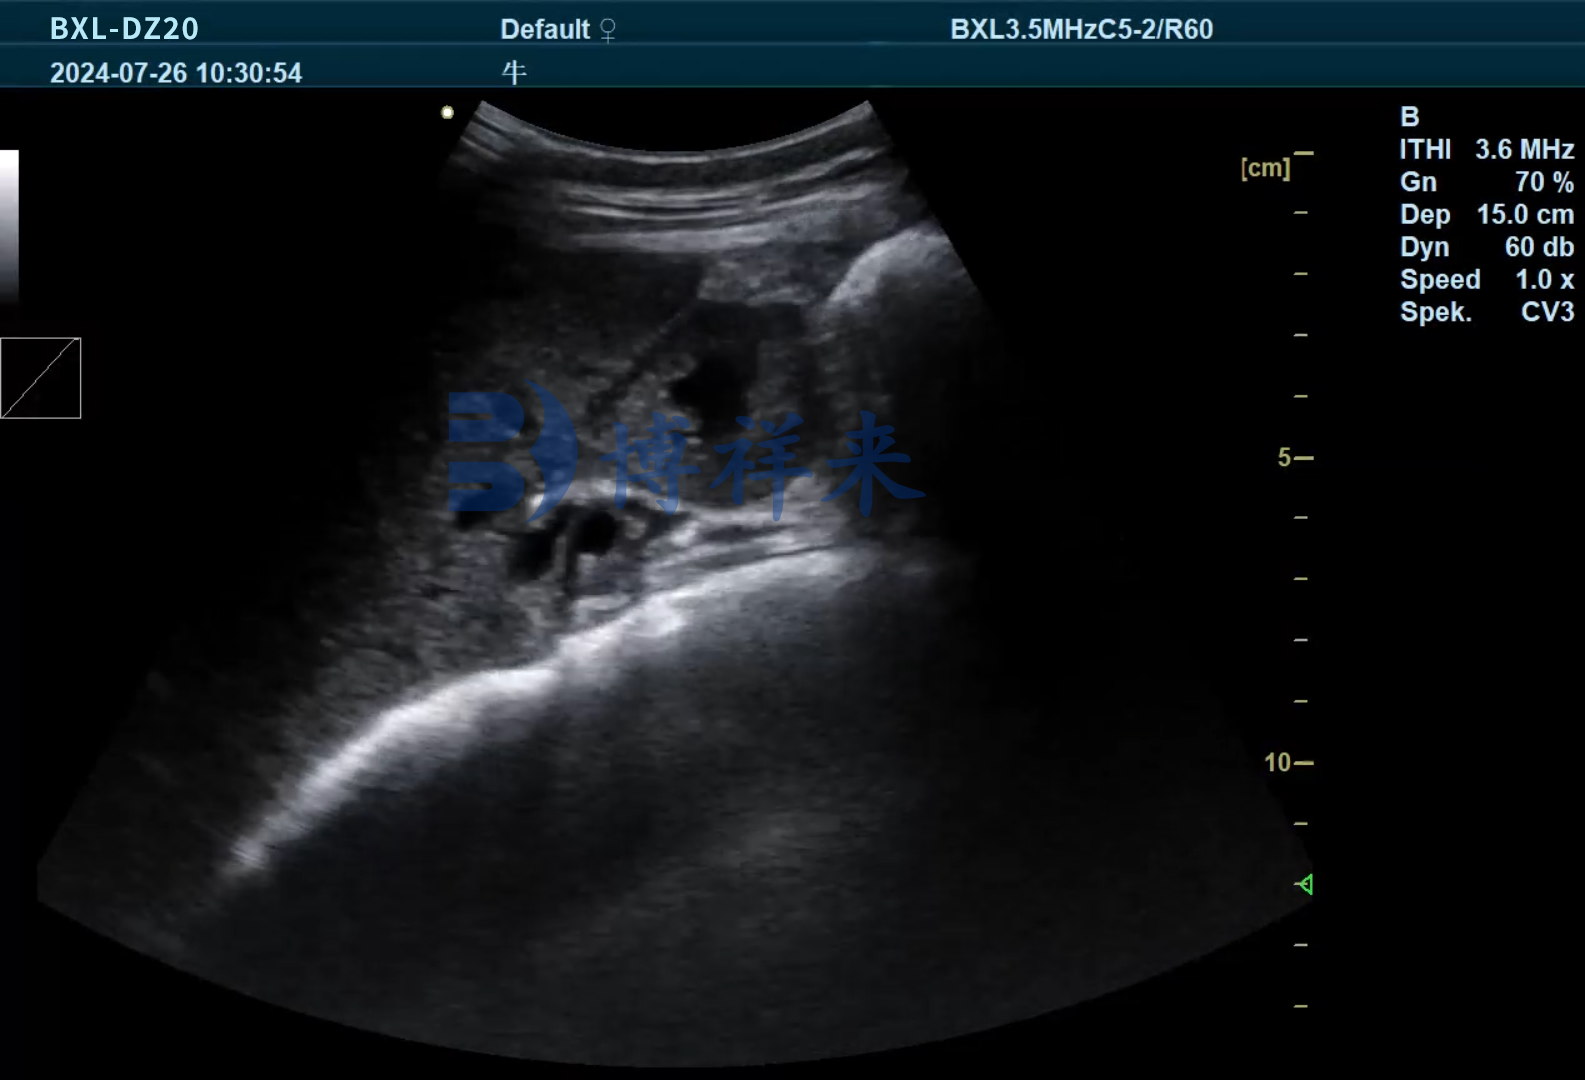

传统上,只有在屠宰时解剖胆囊才能“碰运气”发现牛黄。而现在,借助高分辨率的兽用B超机,可以对牛的肝胆区域进行实时影像观察,提前发现以下异常信号:

作为专业兽用B超设备制造商,博祥来推出的BXL-DZ20等型号,配备高清成像微凸探头,特别适用于肝胆区域的深层组织观察,可用于检测胆囊结石、肝脏病变、卵巢状态等,是养殖场全面掌握牛只健康和附加价值的理想工具。